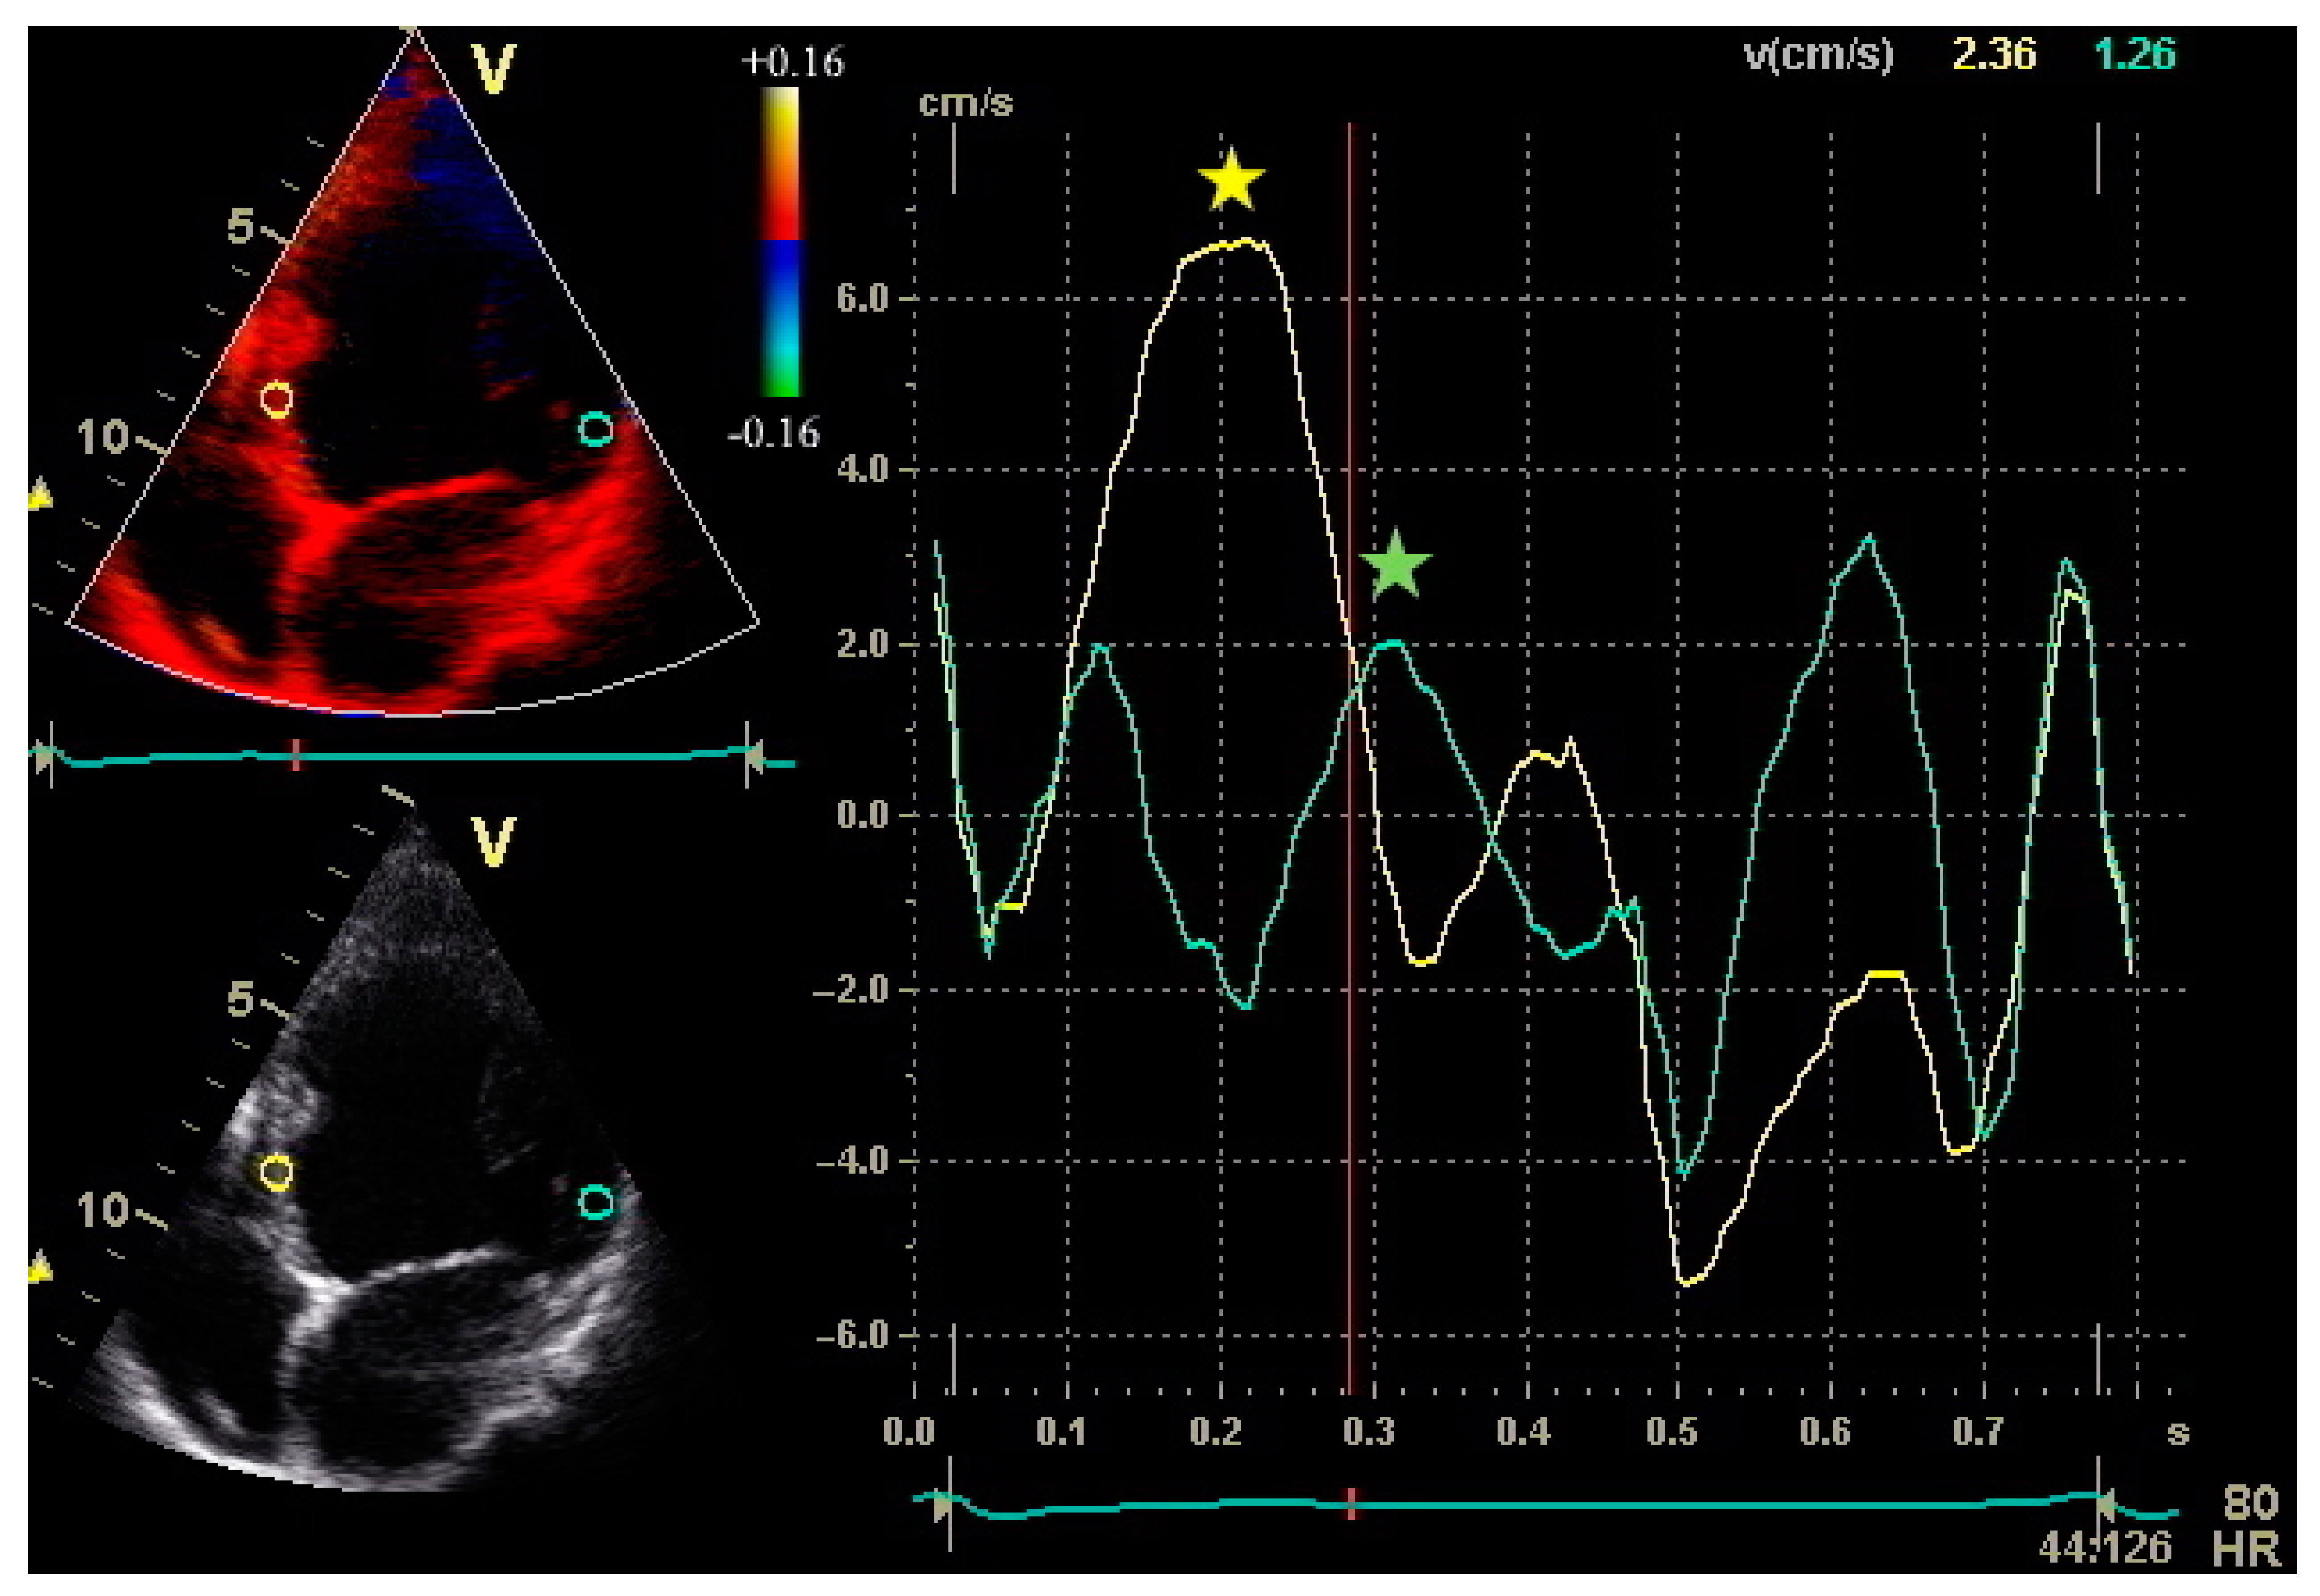

2.1. Assessment of LV Function and Dyssynchrony

- Yu, C.M.; Chau, E.; Sanderson, J.E.; Fan, K.; Tang, M.O.; Fung, W.H.; Lin, H.; Kong, S.L.; Lam, Y.M.; Hill, M.R.; et al. Tissue Doppler echocardiographic evidence of reverse remodeling and improved synchronicity by simultaneously delaying regional contraction after biventricular pacing therapy in heart failure. Circulation 2002, 105, 438–445. [Google Scholar] [CrossRef] [Green Version]

- Delgado, V.; Ypenburg, C.; van Bommel, R.J.; Tops, L.F.; Mollema, S.A.; Marsan, N.A.; Bleeker, G.B.; Schalij, M.J.; Bax, J.J. Assessment of left ventricular dyssynchrony by speckle tracking strain imaging comparison between longitudinal, circumferential, and radial strain in cardiac resynchronization therapy. J. Am. Coll. Cardiol. 2008, 51, 1944–1952. [Google Scholar] [CrossRef] [Green Version]

- Gorcsan, J., 3rd; Abraham, T.; Agler, D.A.; Bax, J.J.; Derumeaux, G.; Grimm, R.A.; Martin, R.; Steinberg, J.S.; Sutton, M.S.; Yu, C.M.; et al. Echocardiography for cardiac resynchronization therapy: Recommendations for performance and reporting—A report from the American Society of Echocardiography Dyssynchrony Writing Group endorsed by the Heart Rhythm Society. J. Am. Soc. Echocardiogr. 2008, 21, 191–213. [Google Scholar] [CrossRef]